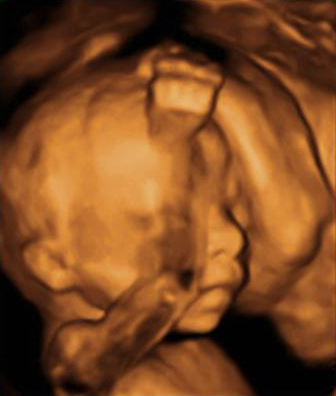

En la 20 semana de gestación, los órganos sexuales del feto, masculinos o femeninos, ya están formados y son visibles, especialmente con una ecografía en 4D. Aquí la imagen ha captado el sexo de un niño.

Ecografía semana 20: sexo masculino

En la imagen podemos ver un feto de 20 semanas y 6 días de gestación del sexo masculino.